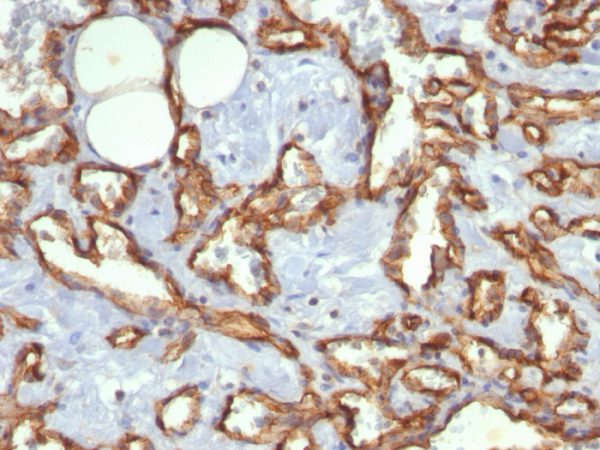

Formalin-fixed, paraffin-embedded human Angiosarcoma stained with CD31 Mouse Monoclonal Antibody (C31.3).

CD31 (PECAM-1) is a transmembrane glycoprotein member of the immunoglobulin supergene family of adhesion molecules. CD31 is expressed by stem cells of the hematopoietic system and is primarily used to identify and concentrate these cells for experimental studies as well as for bone marrow transplantation. Anti-CD31 has shown to be highly specific and sensitive for vascular endothelial cells. Staining of nonvascular tumors (excluding hematopoietic neoplasms) is rare. CD31 MAb reacts with normal, benign, and malignant endothelial cells which make up blood vessel lining. The level of CD31 expression can help to determine the degree of tumor angiogenesis, and a high level of CD31 expression may imply a rapidly growing tumor and potentially a predictor of tumor recurrence.